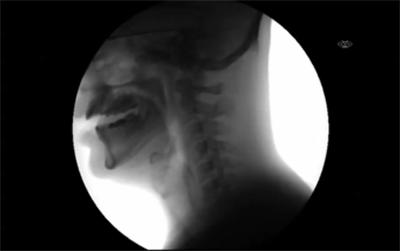

人们喝水的样子